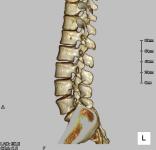

脊椎CT検査

椎体の変形や骨折、配列の乱れ、腫瘍などを任意の断面で観察することができます。

画像処理によって、立体的に表示させることも可能です。